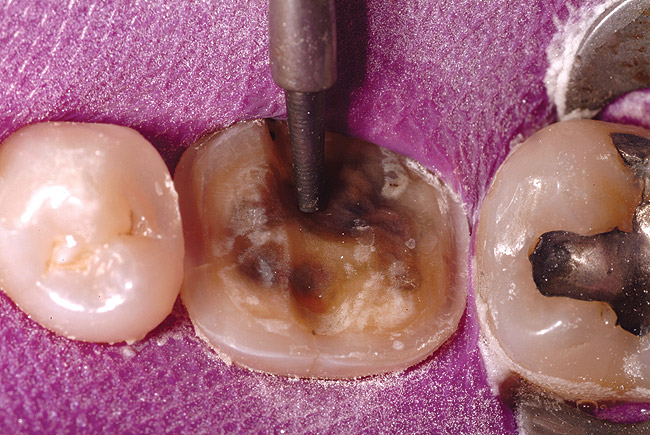

Figure 1a  A patient presents with large direct composite restorations and multiple crack lines in teeth Nos. 18 and 19. Tooth No. 19 was symptomatic to biting pressure.

Figure 1a

Figure 1b  The teeth were prepared for adhesively retained restorations. Note the significant ring of remaining enamel.

Figure 1b

Figure 1c  The final restorations restore and protect the compromised cusps.

Figure 1c